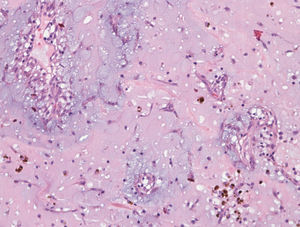

Dados histológicosAs características histológicas observadas nestes 40 casos enquadram-se nas habitualmente descritas para esta entidade9–12: células mesenquimatosas alongadas, fusiformes, estreladas e poligonais num estroma mixoide (Figura 5). O citoplasma das células do mixoma é relativamente escasso e eosinofílico. Os núcleos são ovais, redondos ou alongados. As mitoses são raríssimas e típicas. A celularidade é variável. As células encontram-se isoladas, em pequenos ninhos, cordões ou anéis, estes últimos frequentemente à volta de vasos, em camada única ou várias camadas. Observámos mais frequentemente os padrões perivascular e em pequenos ninhos. Num único caso, encontrámos estruturas epitelioides, glanduliformes; também só num caso observámos estruturas semelhantes a células gigantes multinucleadas, mas que podem corresponder a agregados de células.

Para lá das células de MC, observa-se frequentemente a existência de um número variável de macrófagos, linfócitos, plasmócitos, leucócitos polimorfonucleares, células dendríticas e mastócitos, e podem ainda identificar-se fibroblastos, miofibroblastos e células musculares lisas. Na nossa série, o infiltrado inflamatório observado foi predominantemente linfoplasmocitário, contendo também neutrófilos em 13 casos e eosinófilos em 4; a inflamação foi considerada de moderada a intensa em 16 casos (40%) e ligeira ou ausente nos restantes.

O estroma mixoide é positivo na coloração pelo azul de alcião (contém mucinas ácidas) e pode conter quantidades variáveis de colagénio e elastina. A vascularização é, em geral, abundante, os vasos são desprovidos de pericitos e podem existir vasos cavernosos. São frequentes o extravasamento de eritrócitos, os focos de hemorragia (recente ou organizada), os depósitos de hemossiderina (extra e intracelulares), os corpos de Gamna-Gandy e a presença de áreas quísticas. Na série por nós estudada, observámos hemorragia moderada a intensa em 30 casos (75%, sendo extensa em 32,5% dos tumores) e ligeira ou ausente nos restantes. Em 2 dos casos, observámos hematopoiese extramedular. Em quatro casos, identificámos calcificações e, em dois, ossificação.